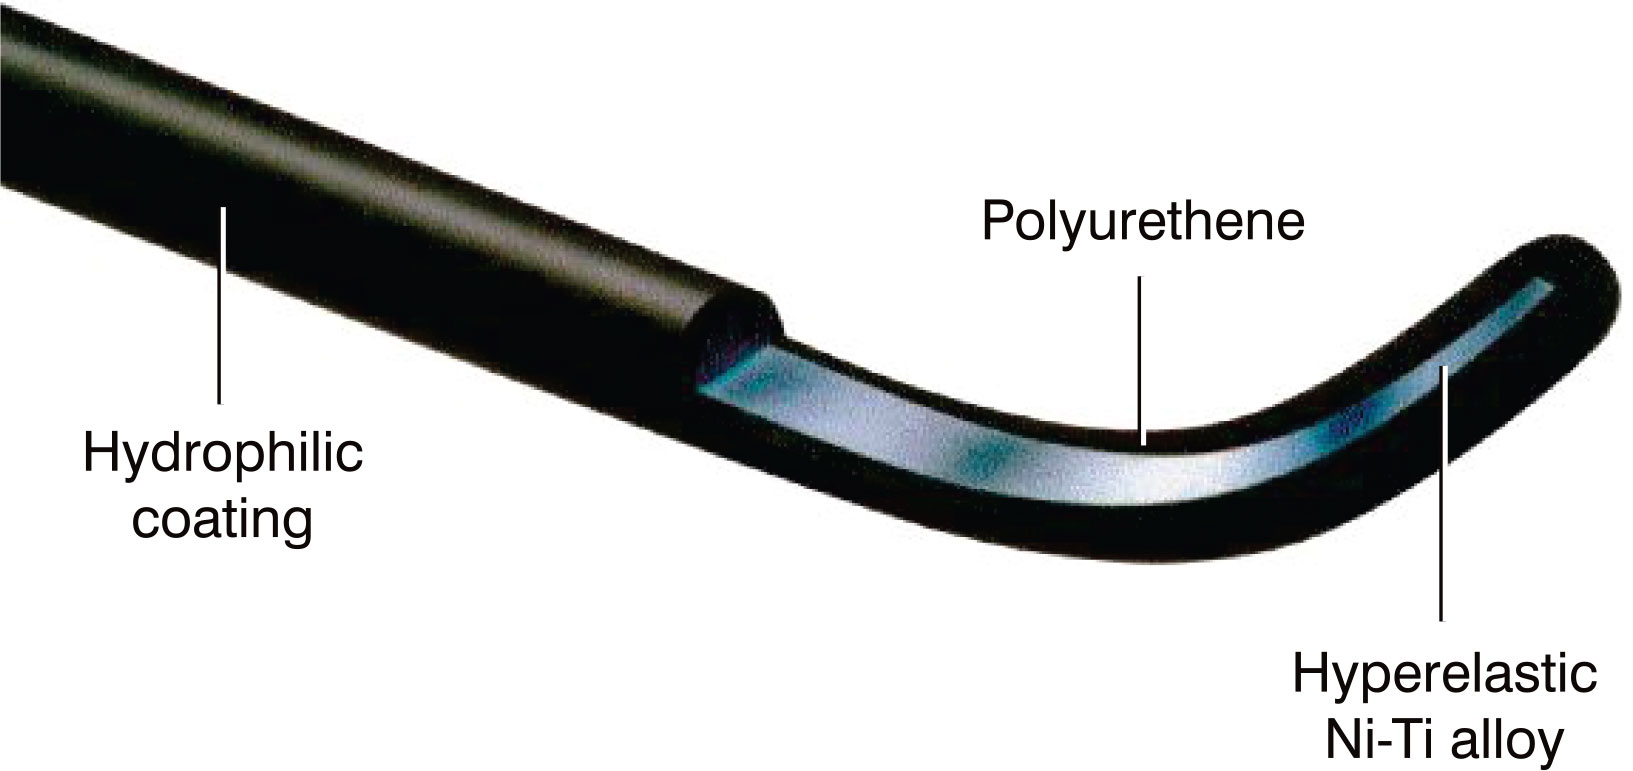

Hydrophilic Guide Wire

Hydrophilic guide wire covered with polyurethane contains tungsten and a hydrophilic polymer coating for complete, low friction manoeuvrability.

Indicated for use of standard angiography in coronary and peripheral cases, catheterization, peripheral angioplasty and stenting (with or without an exchange wire), and sub intimal angioplasty in small, standard or large proximal or distal vessels.

Features

-

Good Trackability & Traceability

Nitinol alloy core resists kinking in tortuous anatomy, allowing for easier and faster tracking. -

Excellent Torque Control

Elastic material and integrated design allows 1:1 torque response to deliver the guidewire into the target vessel quickly -

Durable & Lubricant Performance

Hydrophilic coating offers a durable and smooth approach possible even in tortuous vessels. -

Preeminent Visualization

Tungsten blended polymer ensures great visualization under X- ray